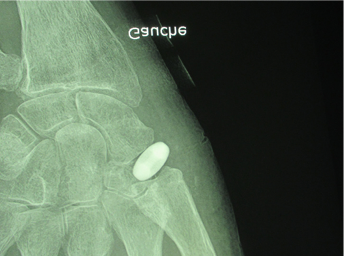

In fact, the patient is usually more bothered by the osteosynthesis material and can often ask for it to be removed. This is why my preferred technique is resurfacing the distal pole of scaphoid using an INCA™ prosthesis (Groupe Lepine). The procedure is quick and easy and can be performed through an anterior portal. The outcomes are good, with mild or zero pain and good finger opposition. Figure 6.